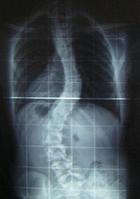

одним із поширених захворювань опорно-рухового апарату у школярів є сколіоз.

Хребет - це

витончена структура, що збоку нагадує витягнуту букву «S». Верхня частина спини

нахилена назовні, а нижня частина спини злегка вигнута всередину. Хоча якщо

дивитися ззаду, хребет буде виглядати прямою лінією від основи шиї до куприка.

Сколіоз - це бічне викривлення хребта. Він з’являється й розвивається в період інтенсивного

зростання організму. Дитина росте не поступово, а толчкообразно, за порівняно

спокійним періодом може відзначатися період активного росту. Особливо це

помітно в період полового дозрівання й у попередній йому. Саме в цей час може

виявитися й бурхливо розвиватися деформація хребта. Наростання деформації

зауважують і батьки. Із закінченням росту наступає стабілізація процесу

розвитку скривлення хребта. Період прогресування сколіозу збігається з

перебуванням дитини в школі. Тому найголовніші причину захворювання в

неправильному навантаженні на хребет при використанні погано підігнаної парти, тривалому

сидінні за комп’ютером. До зовнішніх ознак і симптомів сколіозу відносяться:

Якщо кривизна

сколіозу посилюється, хребет теж починає скручуватися або згинатися, на додаток

до бічного викривлення. Це призводить до того, що ребра на одній стороні тіла

випирають назовні, утворюючи реберний горб. На іншому боці ж формується глибока

западина, що разом деформує тулуб. Важкий ступінь сколіозу може викликати біль

у спині і утруднене дихання.